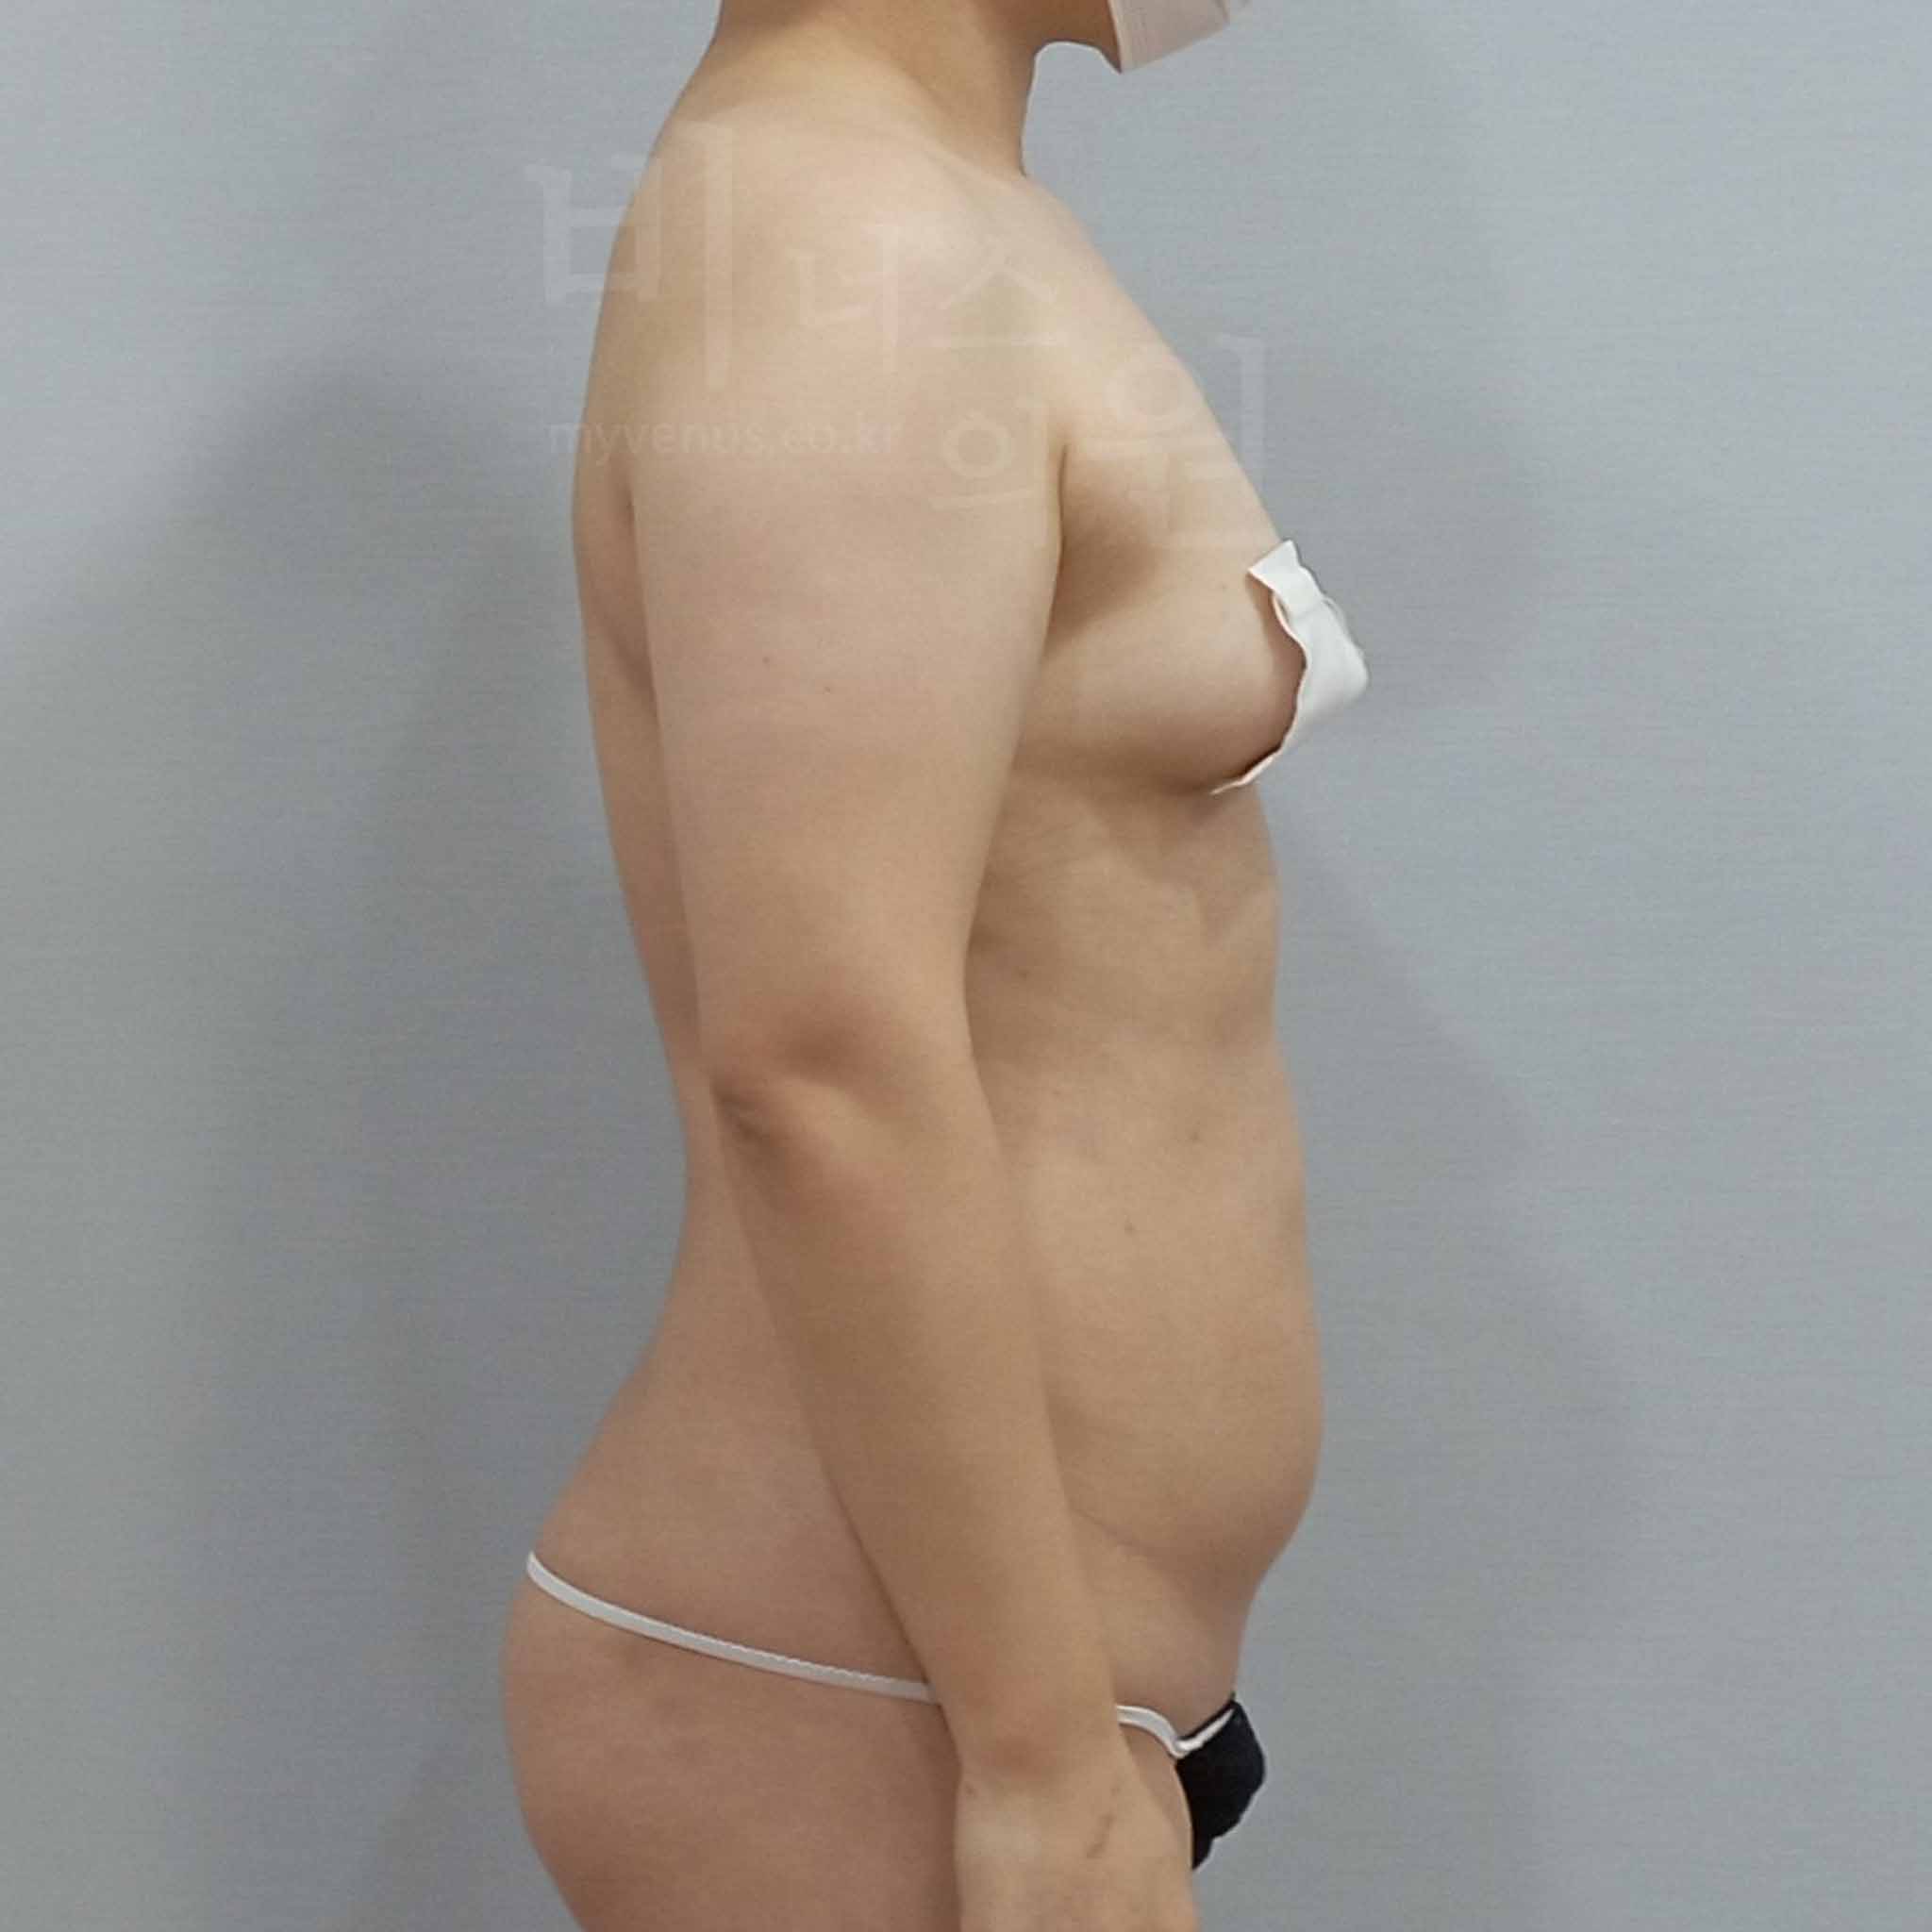

아래 사진은 수술 당일과 수술 후 1주일 경과 시기의 모습으로, 멍과 부기가 남아 있을 수 있는 회복 초기 단계의 과정입니다. 회복 속도와 멍 정도는 개인차가 있을 수 있지만, 대부분은 일상생활에는 무리가 없으며, 팔뚝의 변화는 1개월, 3개월, 6개월에 걸쳐 점진적으로 개선이 됩니다.

연령대 - 50대 초반

경과 기간 - 일주일 경과

수술 부위 - 팔꿈치 포함 원통형 팔뚝, 앞 겨드랑이, 뒷 겨드랑이, 부유방 지방흡입

팔뚝 지방흡입 전 사진

굵고 답답했던 팔뚝

팔뚝 지방흡입 후 사진

슬림하고 탄력 있는 라인

수술 전 - 굵은 팔뚝으로 인해 상체가 부각되어 보이고 옷맵시가 나지 않아 일상에서 불편함과 스트레스를 겪으셨습니다. 다이어트로도 개선되지 않는 팔뚝 지방과 비대칭적인 상체 라인이 주요 고민이었습니다.

수술 후 - 팔둘레가 자연스럽게 감소하며 상체 라인이 슬림하고 균형 있게 개선되었습니다. 울퉁불퉁함이나 흉터 없이 매끄럽고 탄력 있는 결과가 나타났고, 회복 초기임에도 일상생활에 지장이 없는 상태입니다.

팔뚝 지방흡입 전 사진

팔 앞 라인의 굴곡, 많은 지방의 팔뚝 살

팔뚝 지방흡입 후 사진

겨드랑이 애깃살, 팔꿈치까지 매끄럽게

수술 전 - 측면에서 봤을 때, 앞쪽 겨드랑이 애깃살 부위가 지방 축적으로 인해 불룩하게 튀어나와 굴곡진 팔 라인이 고민이셨습니다.

수술 후 - 쉽게 빠지지 않는 군살인 애깃살까지 제거되며 팔 앞 라인이 매끄럽게 개선되었고, 사이즈 감소와 함께 자연스러운 실루엣 변화가 이루어졌습니다.